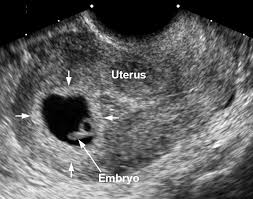

If there is no foetal pole seen at 6 weeks it need not mean the worst and not to worry. Pregnancy was not successful. They said plus or minus a week is within the normal range but we were 3 days past that. Sometimes the foetal pole is not seen on an ultrasound why this is so.

6 weeks 2 days scan no fetal pole. There are several factors involved in the detection of a healthy foetus like the size of the gestational sac menstrual cycle measurement error and so on. Hi everyone so i went for an early scan last week the tech measured me at 6 weeks 2 days due to the size of my gestational sac and we also saw a yolk sac but no fetal pole was seen im worried sick as i do not have many pragnancy symptoms the tech did not really seem worried she said i was a tad too early but everywhere i read you should. The pregnancy is not viable if however you go to the follow up ultrasound and there s still no sign of a fetal pole or a gestational sac which looks like white rim around a clear center a miscarriage has likely occurred.